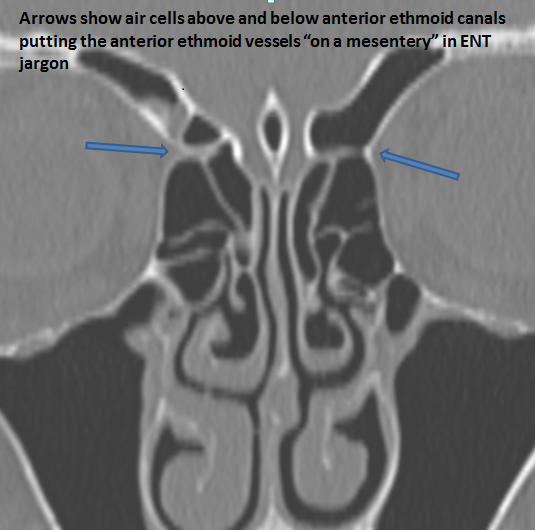

The anterior ethmoid arteries are on a mesentery. [Yes/No]